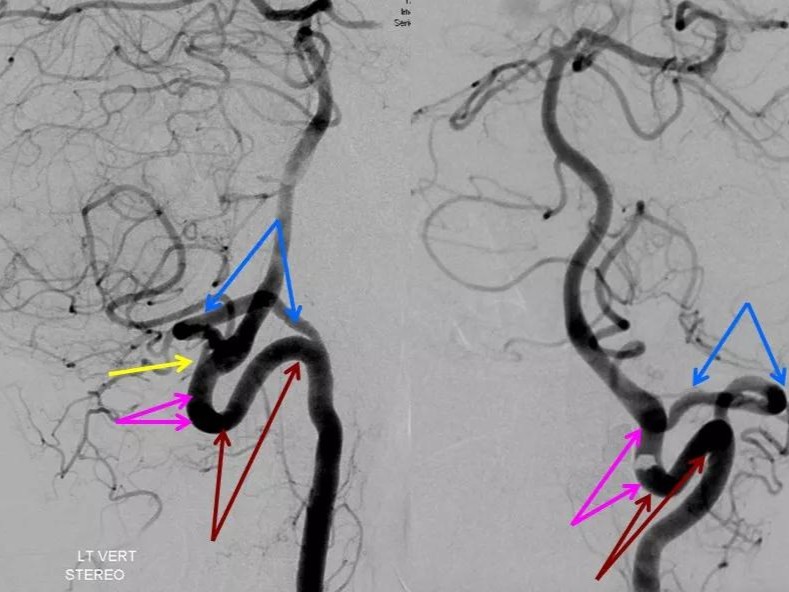

图说:术后开通闭塞右侧椎动脉,基底动脉血流恢复,小脑及脑干功能明显

椎基底动脉系统ctmr及dsa影像解剖

椎-基底动脉系统ct,mr及dsa影像解剖